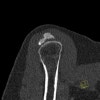

초음파 또는 CT나 MRI를 촬영할 필요는 없으나, 이들 검사로는 동반된 회전근개 파열 등을 감별할 수 있습니다(석회화는 CT가 우수, MRI에서 찾기 어렵습니다).

CT : 석회화 건염(Calcific tendinitis, Calcific tendonitis)